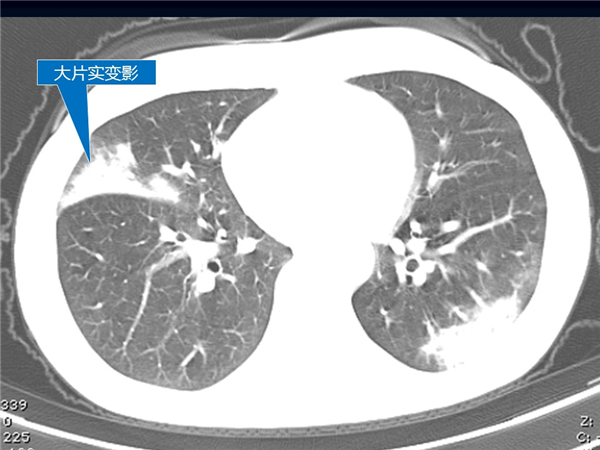

【病例分享】新型冠狀病毒感染肺部CT影像4例(常德市第一人民醫(yī)院)

幻燈片7.jpg